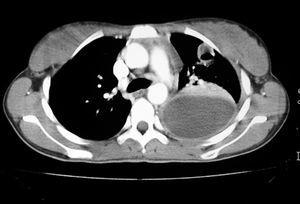

En la radiografía y tomografía axial computarizada (TAC) de tórax (figs. 1 y 2) se apreciaba una imagen redondeada y cavitada en lóbulo superior izquierdo, con un extenso derrame pleural del mismo lado.

Figura 2. Tomografía axial computarizada (TAC) pulmonar: se observa colección pleural izquierda con engrosamiento pleural difuso que ocasiona atelectasia del parénquima pulmonar adyacente. Nódulo cavitado con pequeño nivel hidroaéreo en lóbulo superior izquierdo.